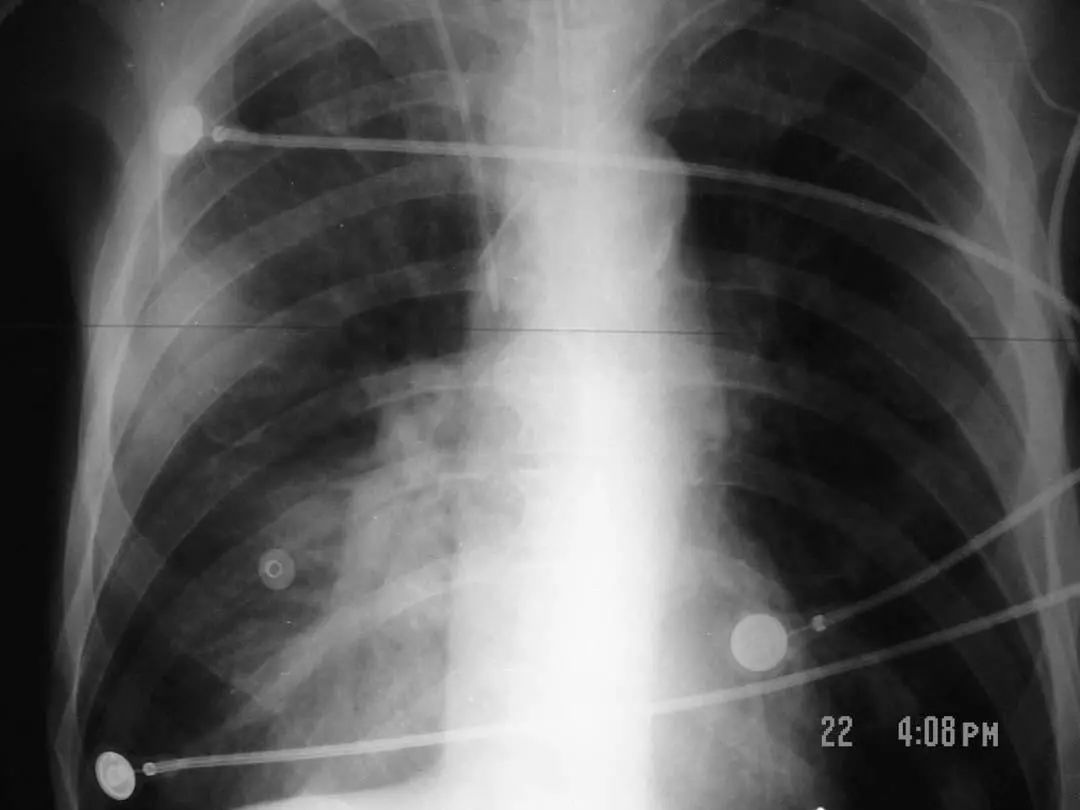

图1.4 53岁的严重军团菌肺炎患者。胸片显示双肺下叶致密实变。